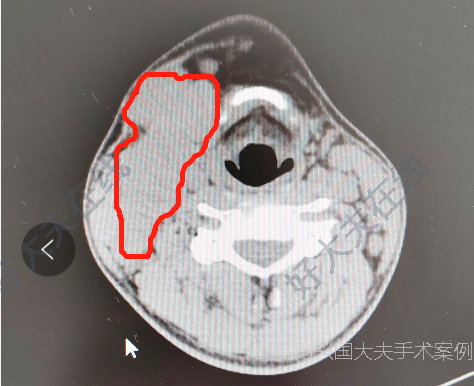

頸部腫塊

鎮(zhèn)江市第一人民醫(yī)院科普號(hào)2023年05月20日265